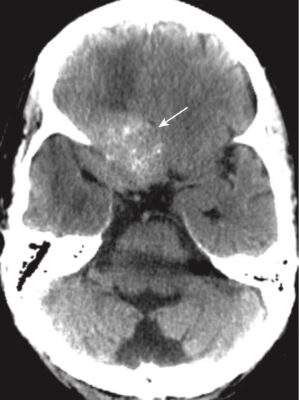

Đột quỵ do xuất huyết (Hemorrhagic Stroke)

- Trong phần lớn các trường hợp, có tăng huyết áp kèm theo. Khoảng 60% trường hợp xuất huyết do tăng huyết áp xảy ra ở hạch nền. Các vùng khác thường liên quan là đồi thị, cầu não và tiểu não (Hình 18).

- Nhận biết xuất huyết trong não (nói chung):

- Máu tươi mới thoát mạch hematocrit bình thường có thể nhìn thấy như là tăng tín hiệu trên phim chụp CT não không cản quang ngay sau biến cố (xem Hình 18). Điều này được cho là do protein trong máu (chủ yếu là hemoglobin).

- Phân tán máu vào hệ thống não thất có thể xảy ra trong chảy máu não do tăng huyết áp (xem Hình 11).

- Khi cục máu đông bắt đầu hình thành, máu trở nên đậm hơn trong khoảng 3 ngày do cục máu đông bị mất nước.

- Sau ngày thứ 3, cục máu đông giảm đậm độ và không nhìn thấy được trong vài tuần tiếp theo. Cục máu đông giảm đậm độ từ bên ngoài vào trong do đó nó có vẻ như co rút lại.

- Sau khoảng 2 tháng, có thể chỉ còn lại một vùng nhỏ giảm đậm độ (Hình 19; Box 1).